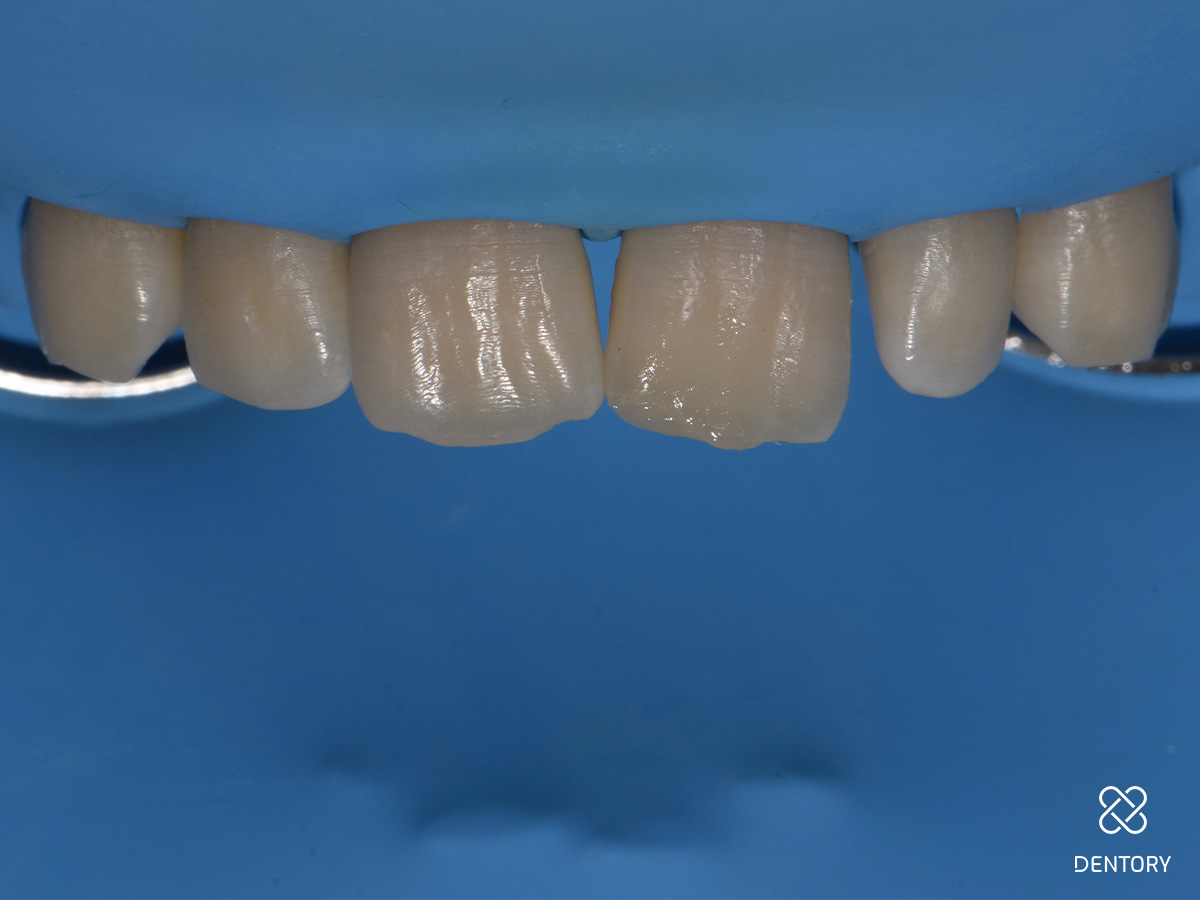

Abbildung 2

Die großzügige Isolierung der Zähne 13-23 mit Kofferdam gewährleistet ein trockenes und störungsfreies Arbeitsumfeld und bietet die Möglichkeit, sich an benachbarten Strukturen zu orientieren.